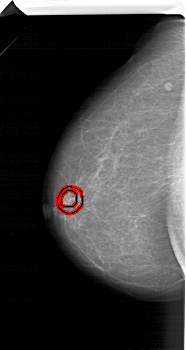

A_1207_1.LEFT_CC

LEFT_CC LINES 6286 PIXELS_PER_LINE 3346 BITS_PER_PIXEL 12 RESOLUTION 43.5 OVERLAY

FILE: A_1207_1.LEFT_CC.OVERLAY

TOTAL_ABNORMALITIES 1

ABNORMALITY 1

LESION_TYPE MASS SHAPE IRREGULAR MARGINS SPICULATED

ASSESSMENT 5

SUBTLETY 1

PATHOLOGY MALIGNANT

TOTAL_OUTLINES 2

BOUNDARY

CORE